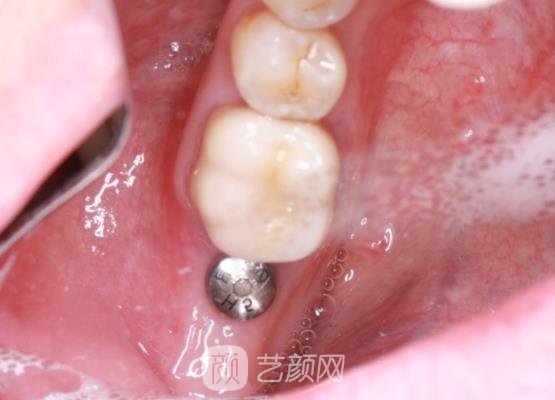

我听了医生的讲解之后真的很心动,随后就让医生为我做了手术,术前医生对我的口腔做了检查,然后还检查了我的身体状况。确定没有什么异常情况之下才为我做的,手术过程当中由于麻醉的缘故,我也没有感觉到疼痛。手术大概进行了2~3个小时左右便已经完成了。

手术刚刚完成之后牙齿出现了一些不舒服的感觉,医生告诉我这是正常的,回到家里要认真的做好口腔的护理,尤其是饭后要及时的漱口,不要吃那些带有辣椒的食物。听了医生的嘱咐之后,我便很放心的就回到家里休养了,在休养的阶段,我一直对于口腔做好了护理。

所以也没有出现不良的反应,现在距离手术已经过去一个半月了,局部恢复的很不错,而且做出来的牙齿就像天生的一样,简直是太令我感到开心了。这一个半月的时间当中,我每天都会精心的护理着,而且多亏了父母的照顾,每天都为我准备一些清淡的饮食。

刚刚昨天我还到医院做了复查的工作,医生也说我恢复的很不错,现在可以正常的咀嚼食物了。医生还对我竖起了大拇指,说我的护理工作做得很到位,同时我也很感谢医生为我的操作,简直是太符合我的要求了。